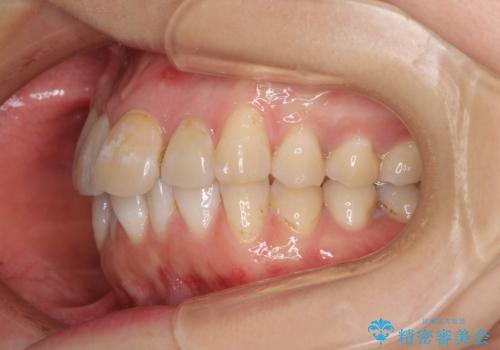

内側に転位していた歯はきれいに歯列に収まり、清掃性が著しく改善しました。

元々神経の失活してしまっている前歯2本は変色が目立つようになってきたため、今後セラミッククラウンによる補綴治療を行う予定です。